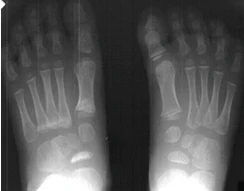

What is Clubfoot?

The medical term for clubfoot is talipes equinovarus and this describes the position of the foot. The feet are pointed down (equinus) and inward (varus).